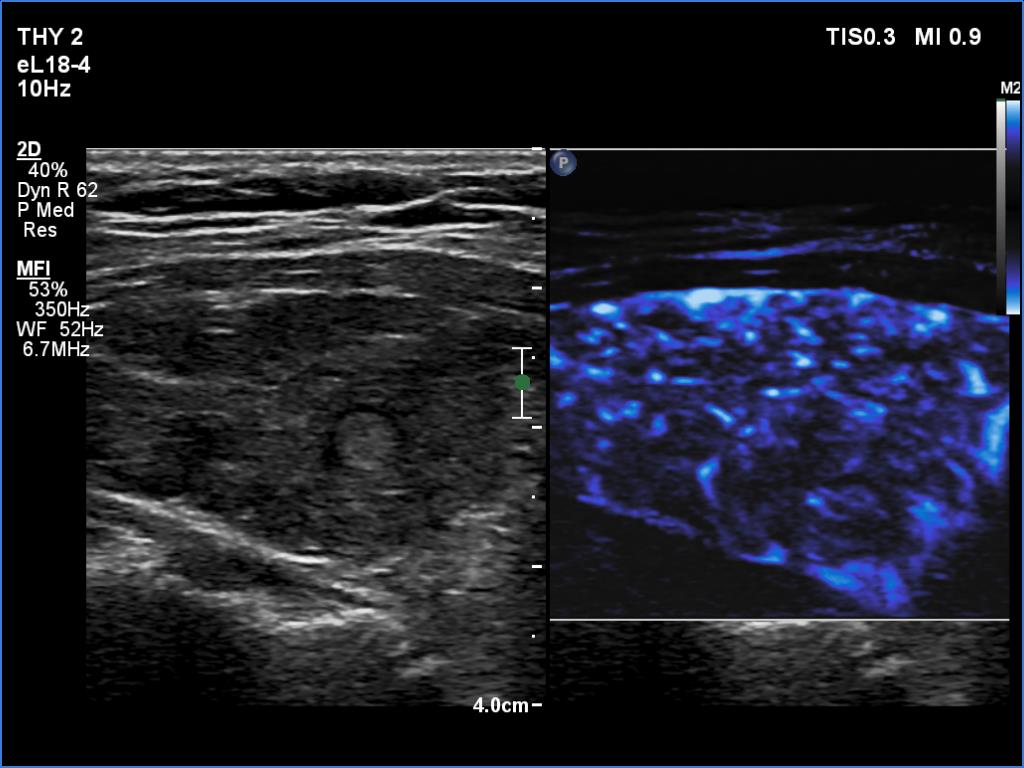

Left lobe, longitudinal scan, microflow imaging. The number of vessels is high.